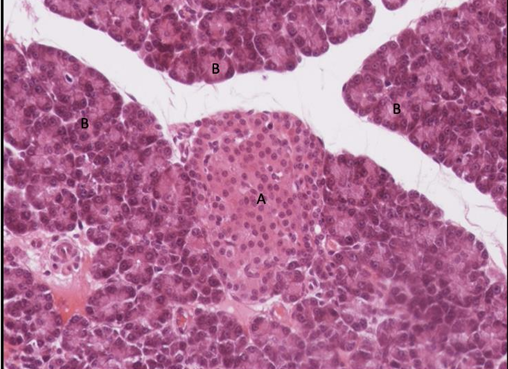

wyspa trzustkowa - wyspy Langerhansa

pęcherzyki trzustkowe